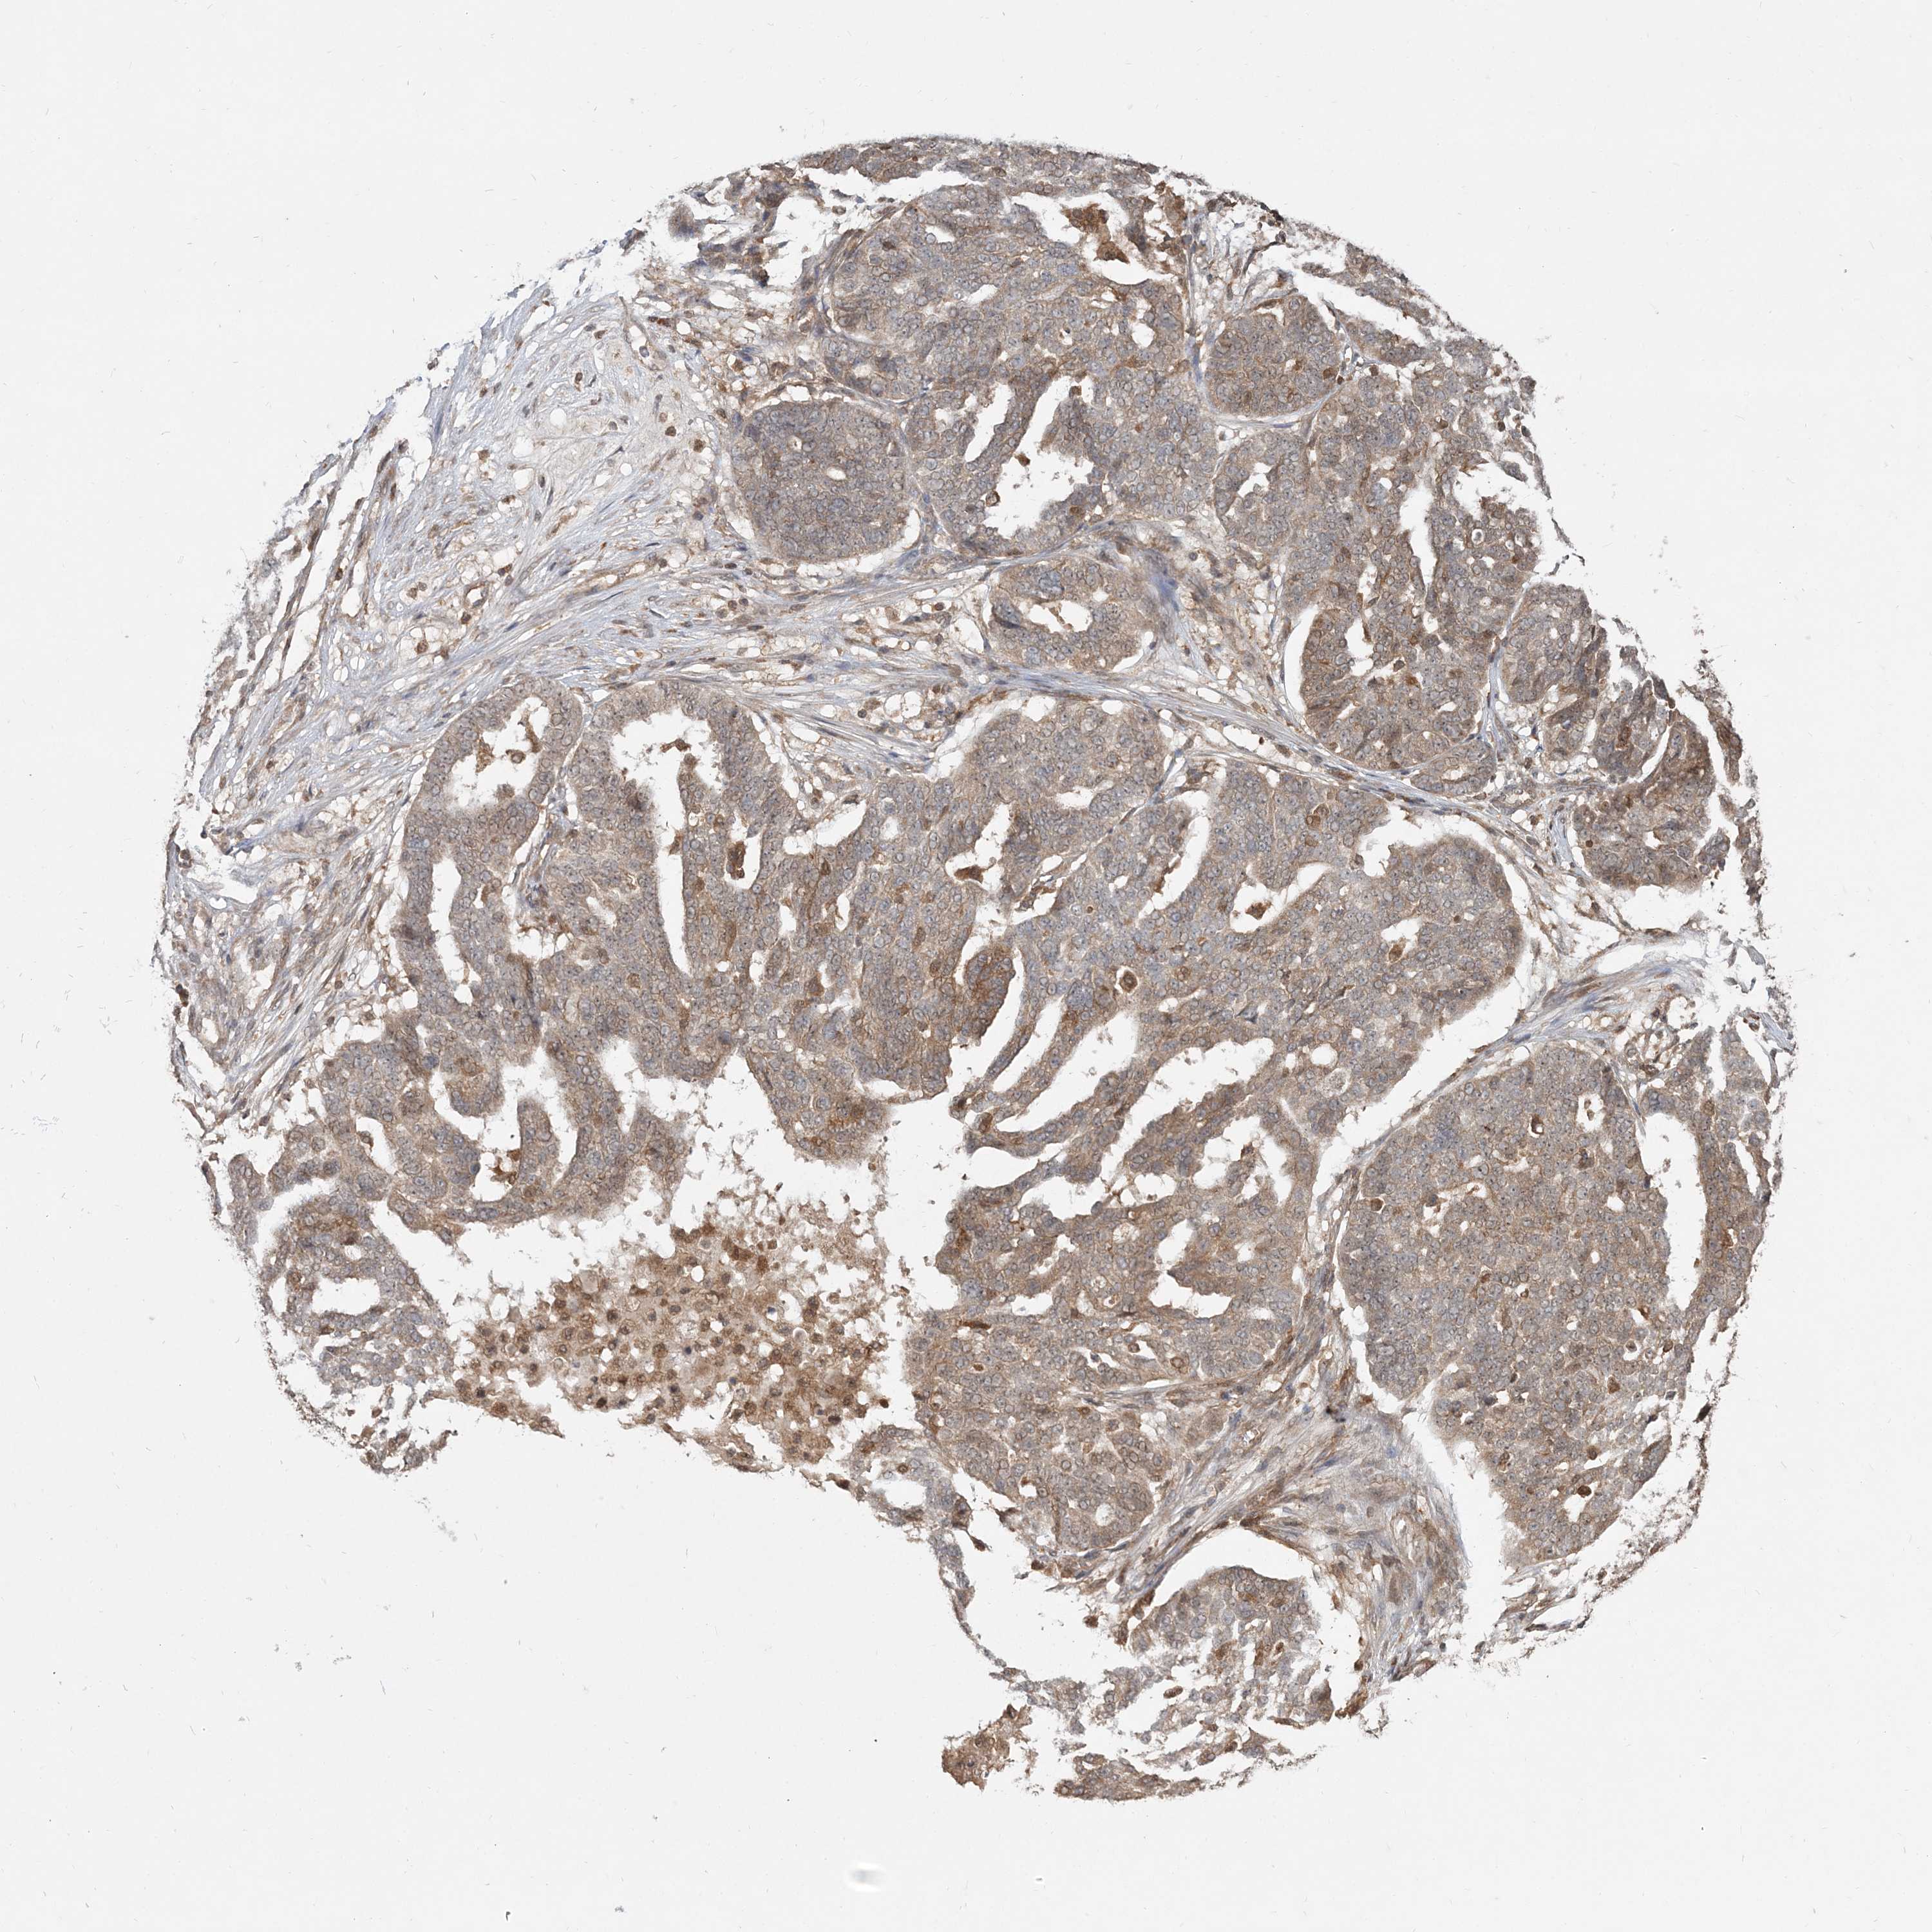

OVARIAN CANCER - Protein expressioni

A mouse-over function shows sample information and annotation data. Click on an image to view it in a full screen mode. Samples can be filtered based on level of antibody staining by selecting one or several of the following categories: high, medium, low and not detected. The assay and annotation is described here.

Note that samples used for immunohistochemistry by the Human Protein Atlas do not correspond to samples in the TCGA dataset.

Antibody stainingi

Antibody staining in the annotated cell types in the current human tissue is reported as not detected, low, medium, or high, based on conventional immunohistochemistry profiling in selected tissues. This score is based on the combination of the staining intensity and fraction of stained cells.

Each image is clickable and will lead to virtual microscopy that enables deeper exploration of all samples and also displays staining intensity scores, fraction scores and subcellular localization as well as patient and tissue information for each sample.

Antibody HPA076632

Antibody CAB037112

Cystadenocarcinoma, serous, NOS

Cystadenocarcinoma, mucinous, NOS

Carcinoma, endometroid

Carcinoma, NOS